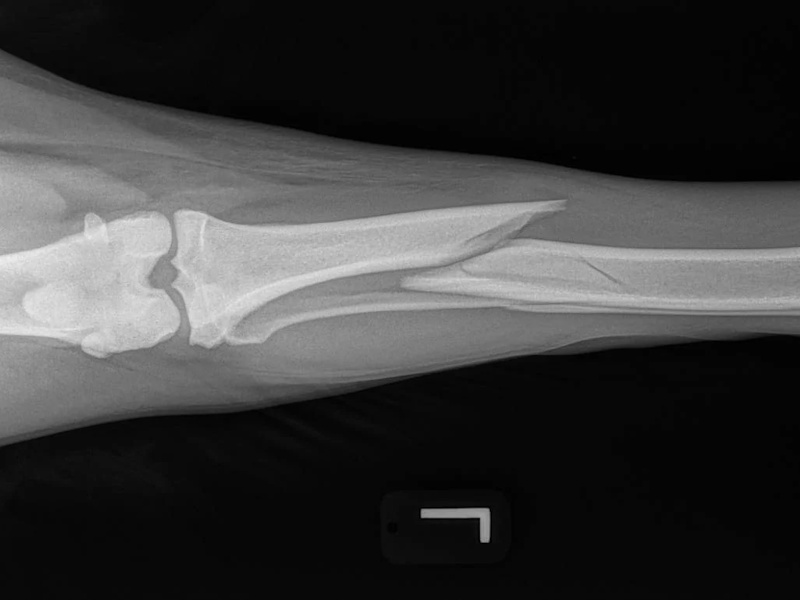

Fore Limb (Humerus, Radius/Ulnar, Metacarpus)

Hind Limb (Pelvis, Femur, Patella, Tibia/Fibula, Lateral Malleolus)